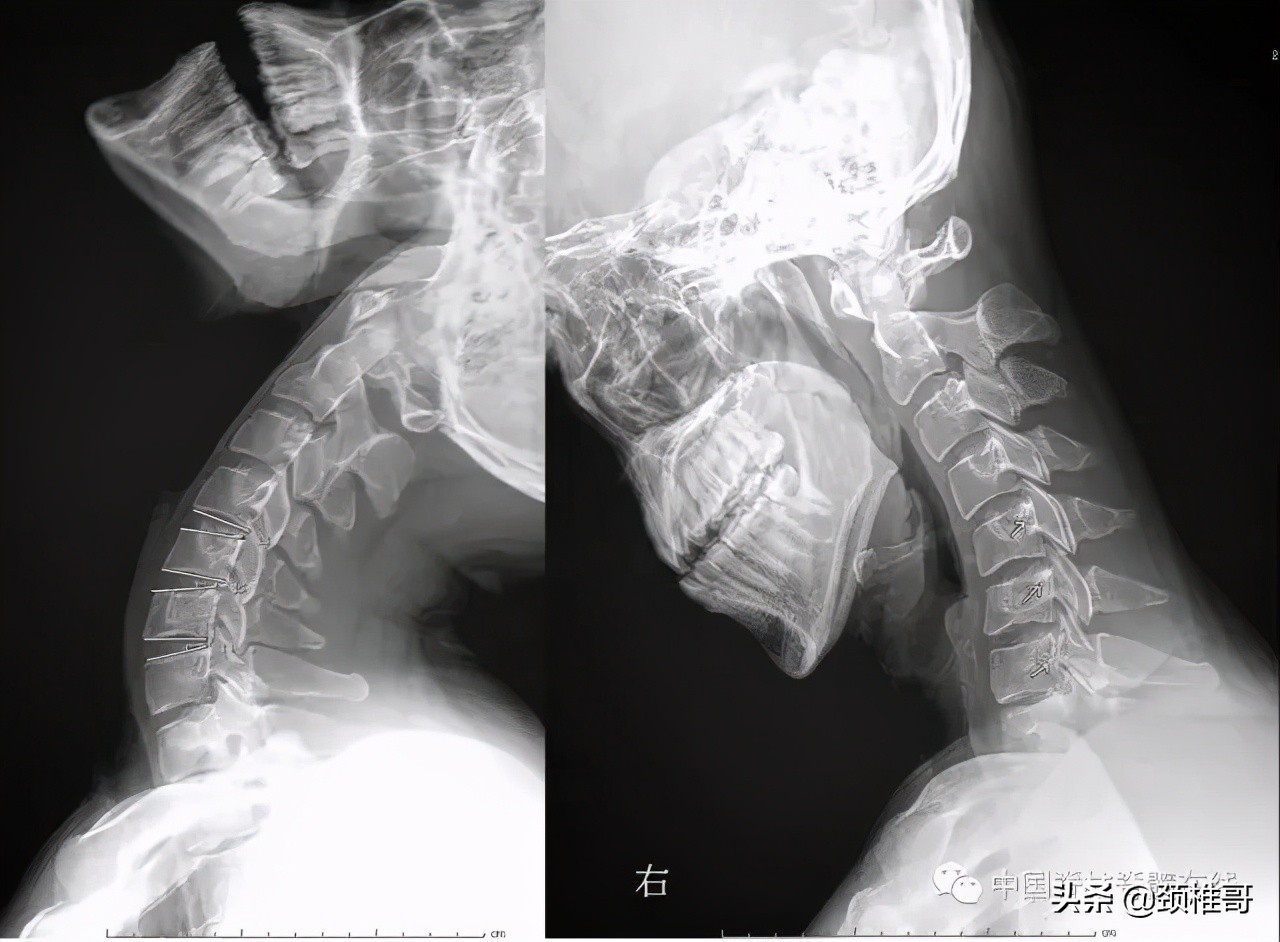

神经根型颈椎病是在肌肉、韧带、椎间盘、骨和关节都已经发生退变,颈椎动态不稳和静态不稳同时存在,代偿性的增生、钙化、韧带肥厚等综合作用下,神经根管狭窄,神经根受压所导致的一种类型颈椎病。我们可以应用中西医药物、适度牵引、理疗等临床治疗方法缓解症状;同时应用主动抗阻运动疗法进行康复训练,增强患者的颈椎周围动态和静态稳定性,筑牢颈椎健康金字塔的根基。如果患者长期坚持康复训练,颈椎稳定了,不需要再通过代偿性增生稳定了,原有的骨质增生就会得到遏制,甚至部分增生的骨质可以被吸收、重塑。这是一位71岁的老人,交感型加神经根型的混合型颈椎病。通过长期的康复训练之后,部分增生的骨质吸收了,颈椎也稳定了,交感神经和神经根的症状都消失了,获得了较好的长期疗效。

长期的康复训练后部分增生的骨刺可以吸收